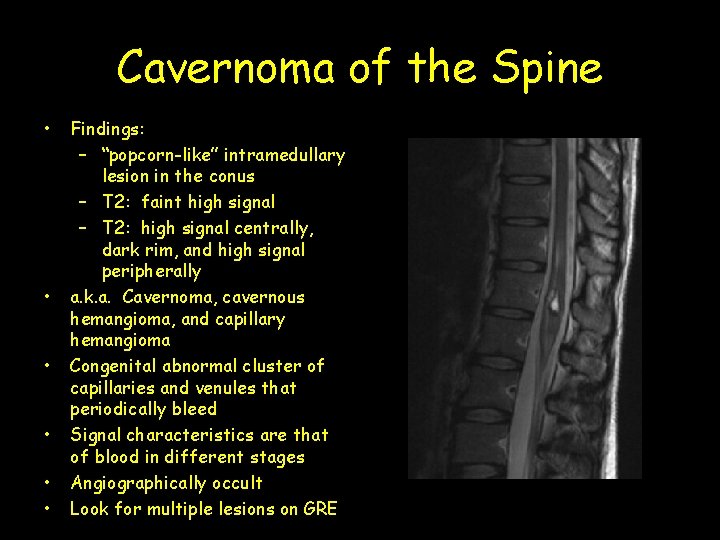

Cavernoma of the Spine • • • Findings: – “popcorn-like” intramedullary lesion in the conus – T 2: faint high signal – T 2: high signal centrally, dark rim, and high signal peripherally a. k. a. Cavernoma, cavernous hemangioma, and capillary hemangioma Congenital abnormal cluster of capillaries and venules that periodically bleed Signal characteristics are that of blood in different stages Angiographically occult Look for multiple lesions on GRE